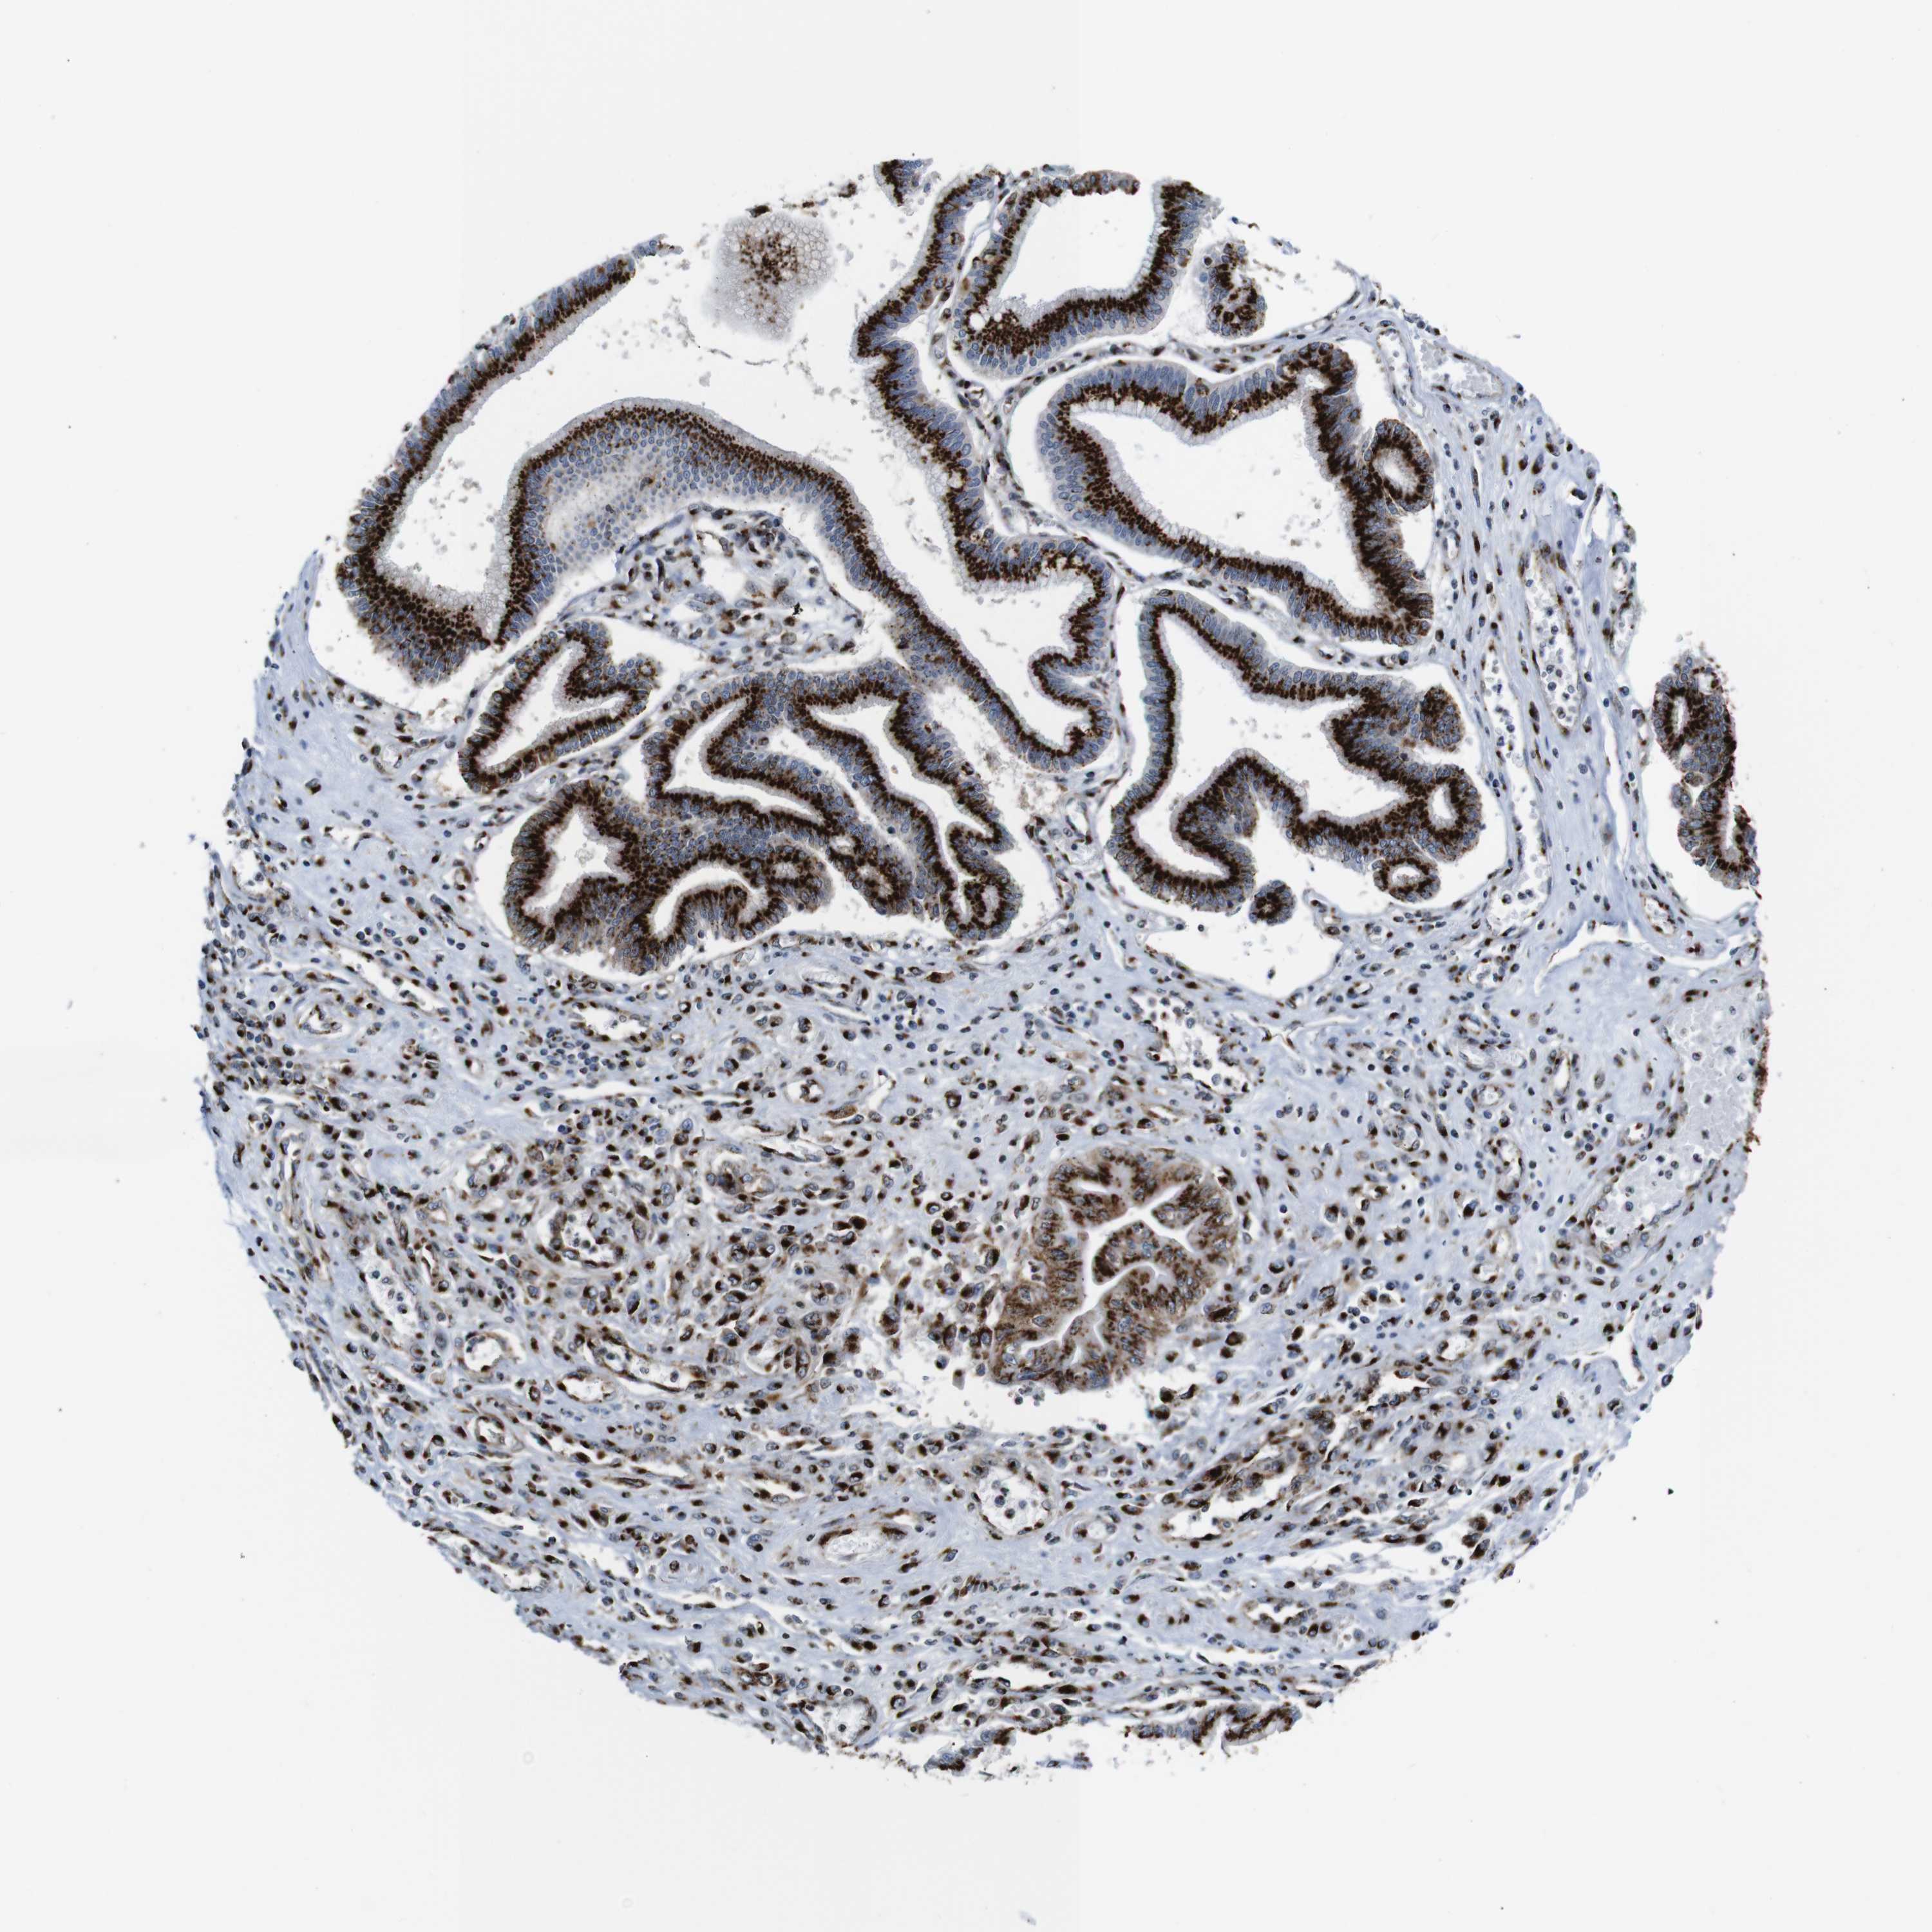

PANCREATIC CANCER - Protein expressioni

A mouse-over function shows sample information and annotation data. Click on an image to view it in a full screen mode. Samples can be filtered based on level of antibody staining by selecting one or several of the following categories: high, medium, low and not detected. The assay and annotation is described here.

Note that samples used for immunohistochemistry by the Human Protein Atlas do not correspond to samples in the TCGA dataset.

Antibody stainingi

Antibody staining in the annotated cell types in the current human tissue is reported as not detected, low, medium, or high, based on conventional immunohistochemistry profiling in selected tissues. This score is based on the combination of the staining intensity and fraction of stained cells.

Each image is clickable and will lead to virtual microscopy that enables deeper exploration of all samples and also displays staining intensity scores, fraction scores and subcellular localization as well as patient and tissue information for each sample.

Antibody HPA012609

Antibody HPA012723

Antibody CAB011489

Staining

High

Medium

Low

Not detected

Intensity

Strong

Moderate

Weak

Negative

Quantity

>75%

75%-25%

<25%

None

Location

Nuclear

Cytoplasmic/membranous

Cytoplasmic/membranous,nuclear

Adenocarcinoma, NOS